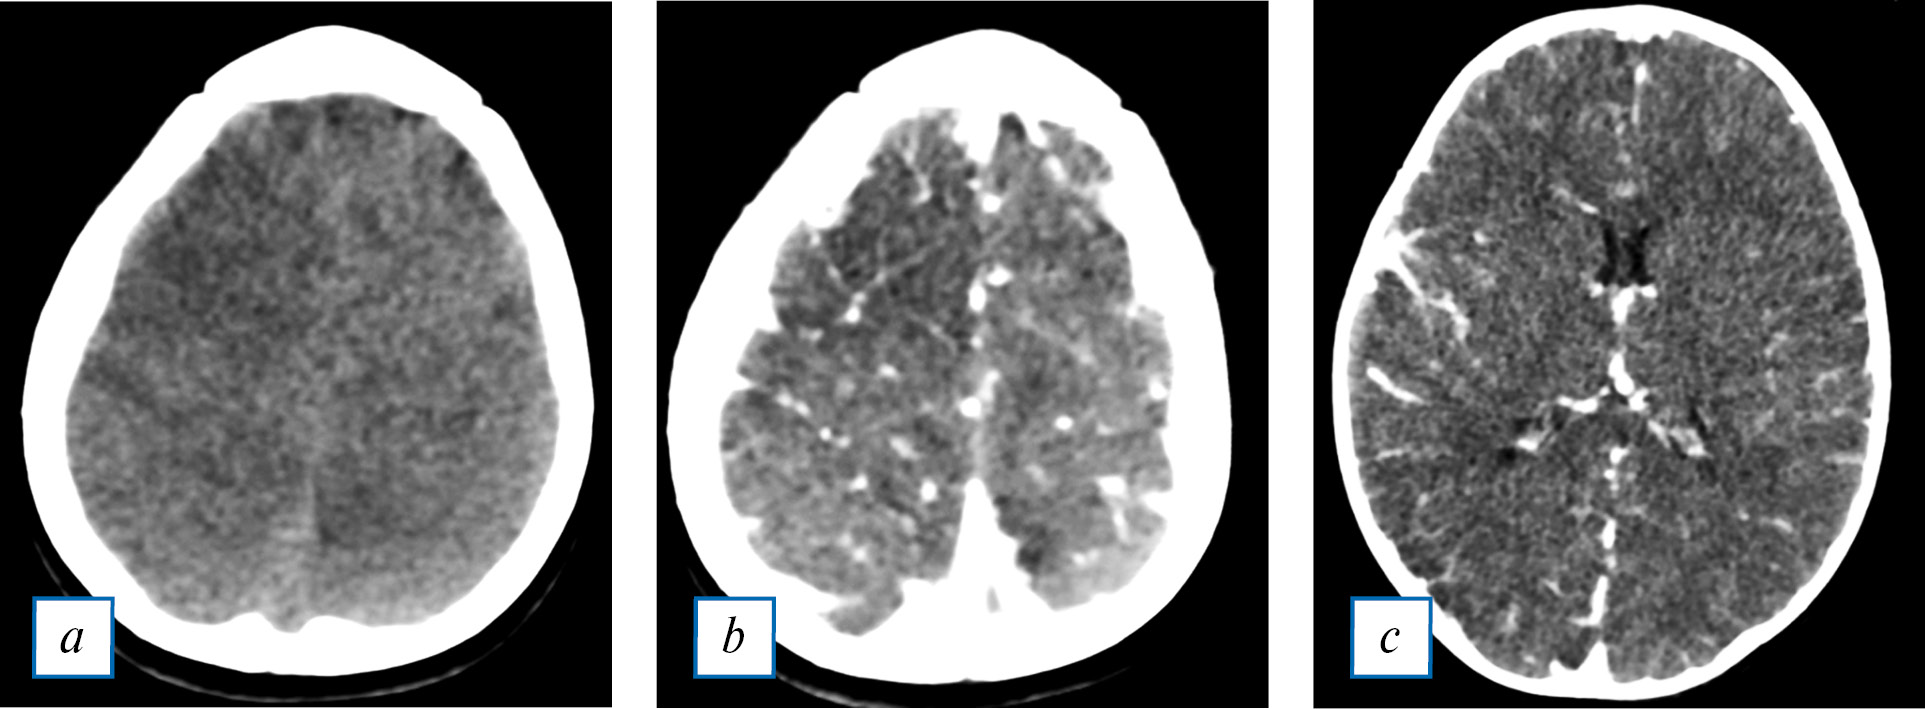

Пример изменений, выявляемых с помощью КТ при БГМ у детей, представлен на рис. 2.

Рис. 2. Бесконтрастная КТ головного мозга пациентки М., 3 мес, с диагнозом бактериального менингита менингококковой этиологии. Динамическое наблюдение в остром периоде с разницей 6 сут (первое наблюдение — в первые сутки поступления, красные стрелки). Нарастание изменений в виде расширения субарахноидального пространства (зеленые стрелки), снижения плотностных показателей серого вещества в области передних и задних рогов боковых желудочков (собственные данные).

Fig. 2. Contrast-free CT of the brain of a patient M, 3 months, diagnosis-bacterial meningitis of meningococcal etiology. Dynamic observation in the acute period with a difference of 6 days (the first observation on the first day of admission, red arrows). Increase of changes in the form of expansion of the subarachnoid space (green arrows), decrease in the density indicators of gray matter in the area of the anterior and posterior horns of the lateral ventricles (own data).